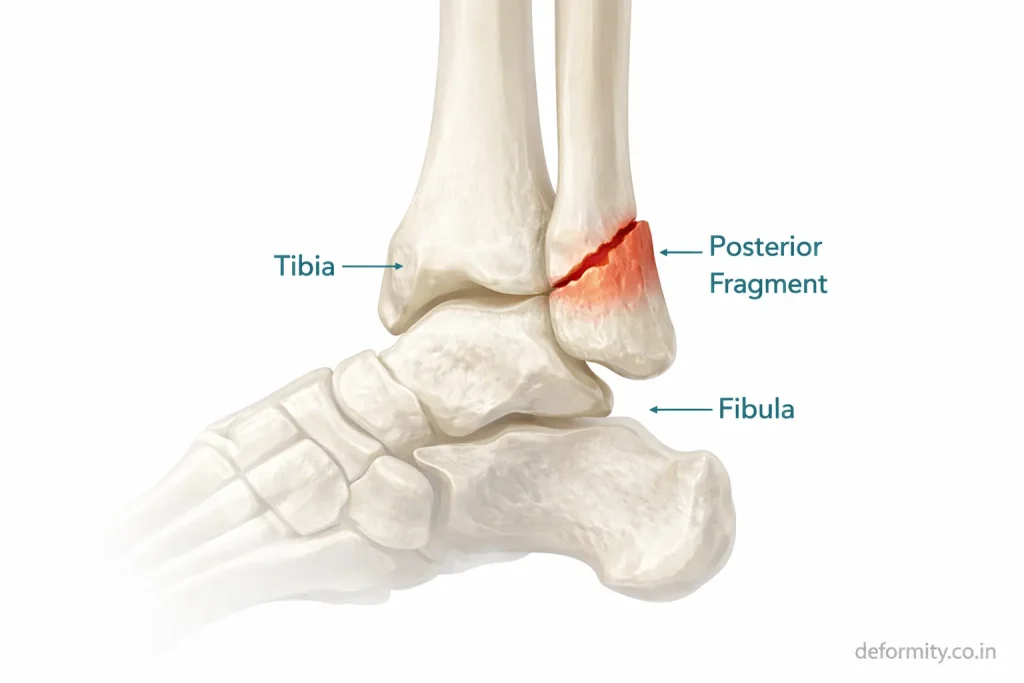

Why the Posterior Malleolus Matters

The posterior malleolus is the back portion of the distal tibia. It forms part of the weight-bearing surface of the ankle joint and provides attachment to the posterior inferior tibiofibular ligament.

Its importance includes:

- Maintaining ankle stability

- Supporting the joint surface

- Preserving syndesmotic integrity

- Preventing talar displacement

When the posterior fragment involves more than 25–30% of the joint surface, surgical fixation is strongly recommended to restore alignment and reduce the risk of arthritis.

In trimalleolar fractures:

- Both sides of the ankle break

- The posterior tibial fragment detaches

- Syndesmotic ligaments may be injured

- The talus may shift out of alignment

Because all structural supports are compromised, joint congruity must be restored surgically.